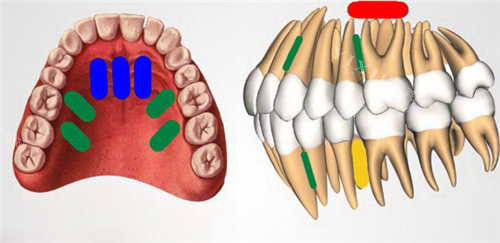

六、根管治疗项目收费参考

根据根管数量与治疗难度定价:

前牙根管治疗:600 元起。前牙多为单根管,治疗相对简单,消除牙髓炎症,保留患牙。

前磨牙根管治疗(单根管):800 元起。根管系统比前牙复杂,治疗流程清晰,医生操作熟练。

前磨牙根管治疗(双根管):1000 元起。分别清理、消毒、充填两根管,确保治疗结果。

磨牙根管治疗(三根管):1500 元起。磨牙承担主要咀嚼功能,根管多且弯曲,治疗难度大,考验医生经验与技术。

磨牙根管治疗(四根管):1800 元起。增加根管,治疗时间长、操作精细度要求更高。

显微根管治疗(加收):500 元起。借助根管显微镜,清晰观察根管内部,提高复杂根管病例治疗可行性。

根管治疗后建议做牙冠修复,保护患牙。